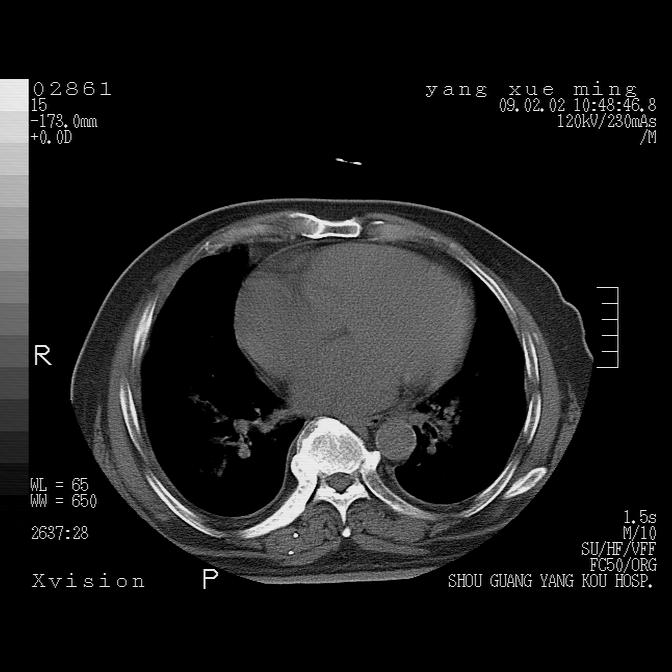

以下是引用lkc8963在2009-2-3 20:11:00的发言:[br]1)右上肺陈旧病灶。2)右下肺团块及团片影,影像表现符合感染。3)左心增大,左冠脉钙化,符合冠心病。4)双侧肺门扩大,以左侧为著,肺动脉干略粗,左上肺局限性气肿,为谨慎起见,需除肿瘤,建议增强。

以下是引用zbp537在2009-2-3 19:08:00的发言:[br]我诊断为肺泡性肺水肿。[br]诊断依据:[br]1、心影普遍增大,肺血管增粗,并见絮状高密度影,肺门改变显著。[br]2、临床上表现胸闷咳嗽,无发烧,不是一个典型的肺部感染的病史。